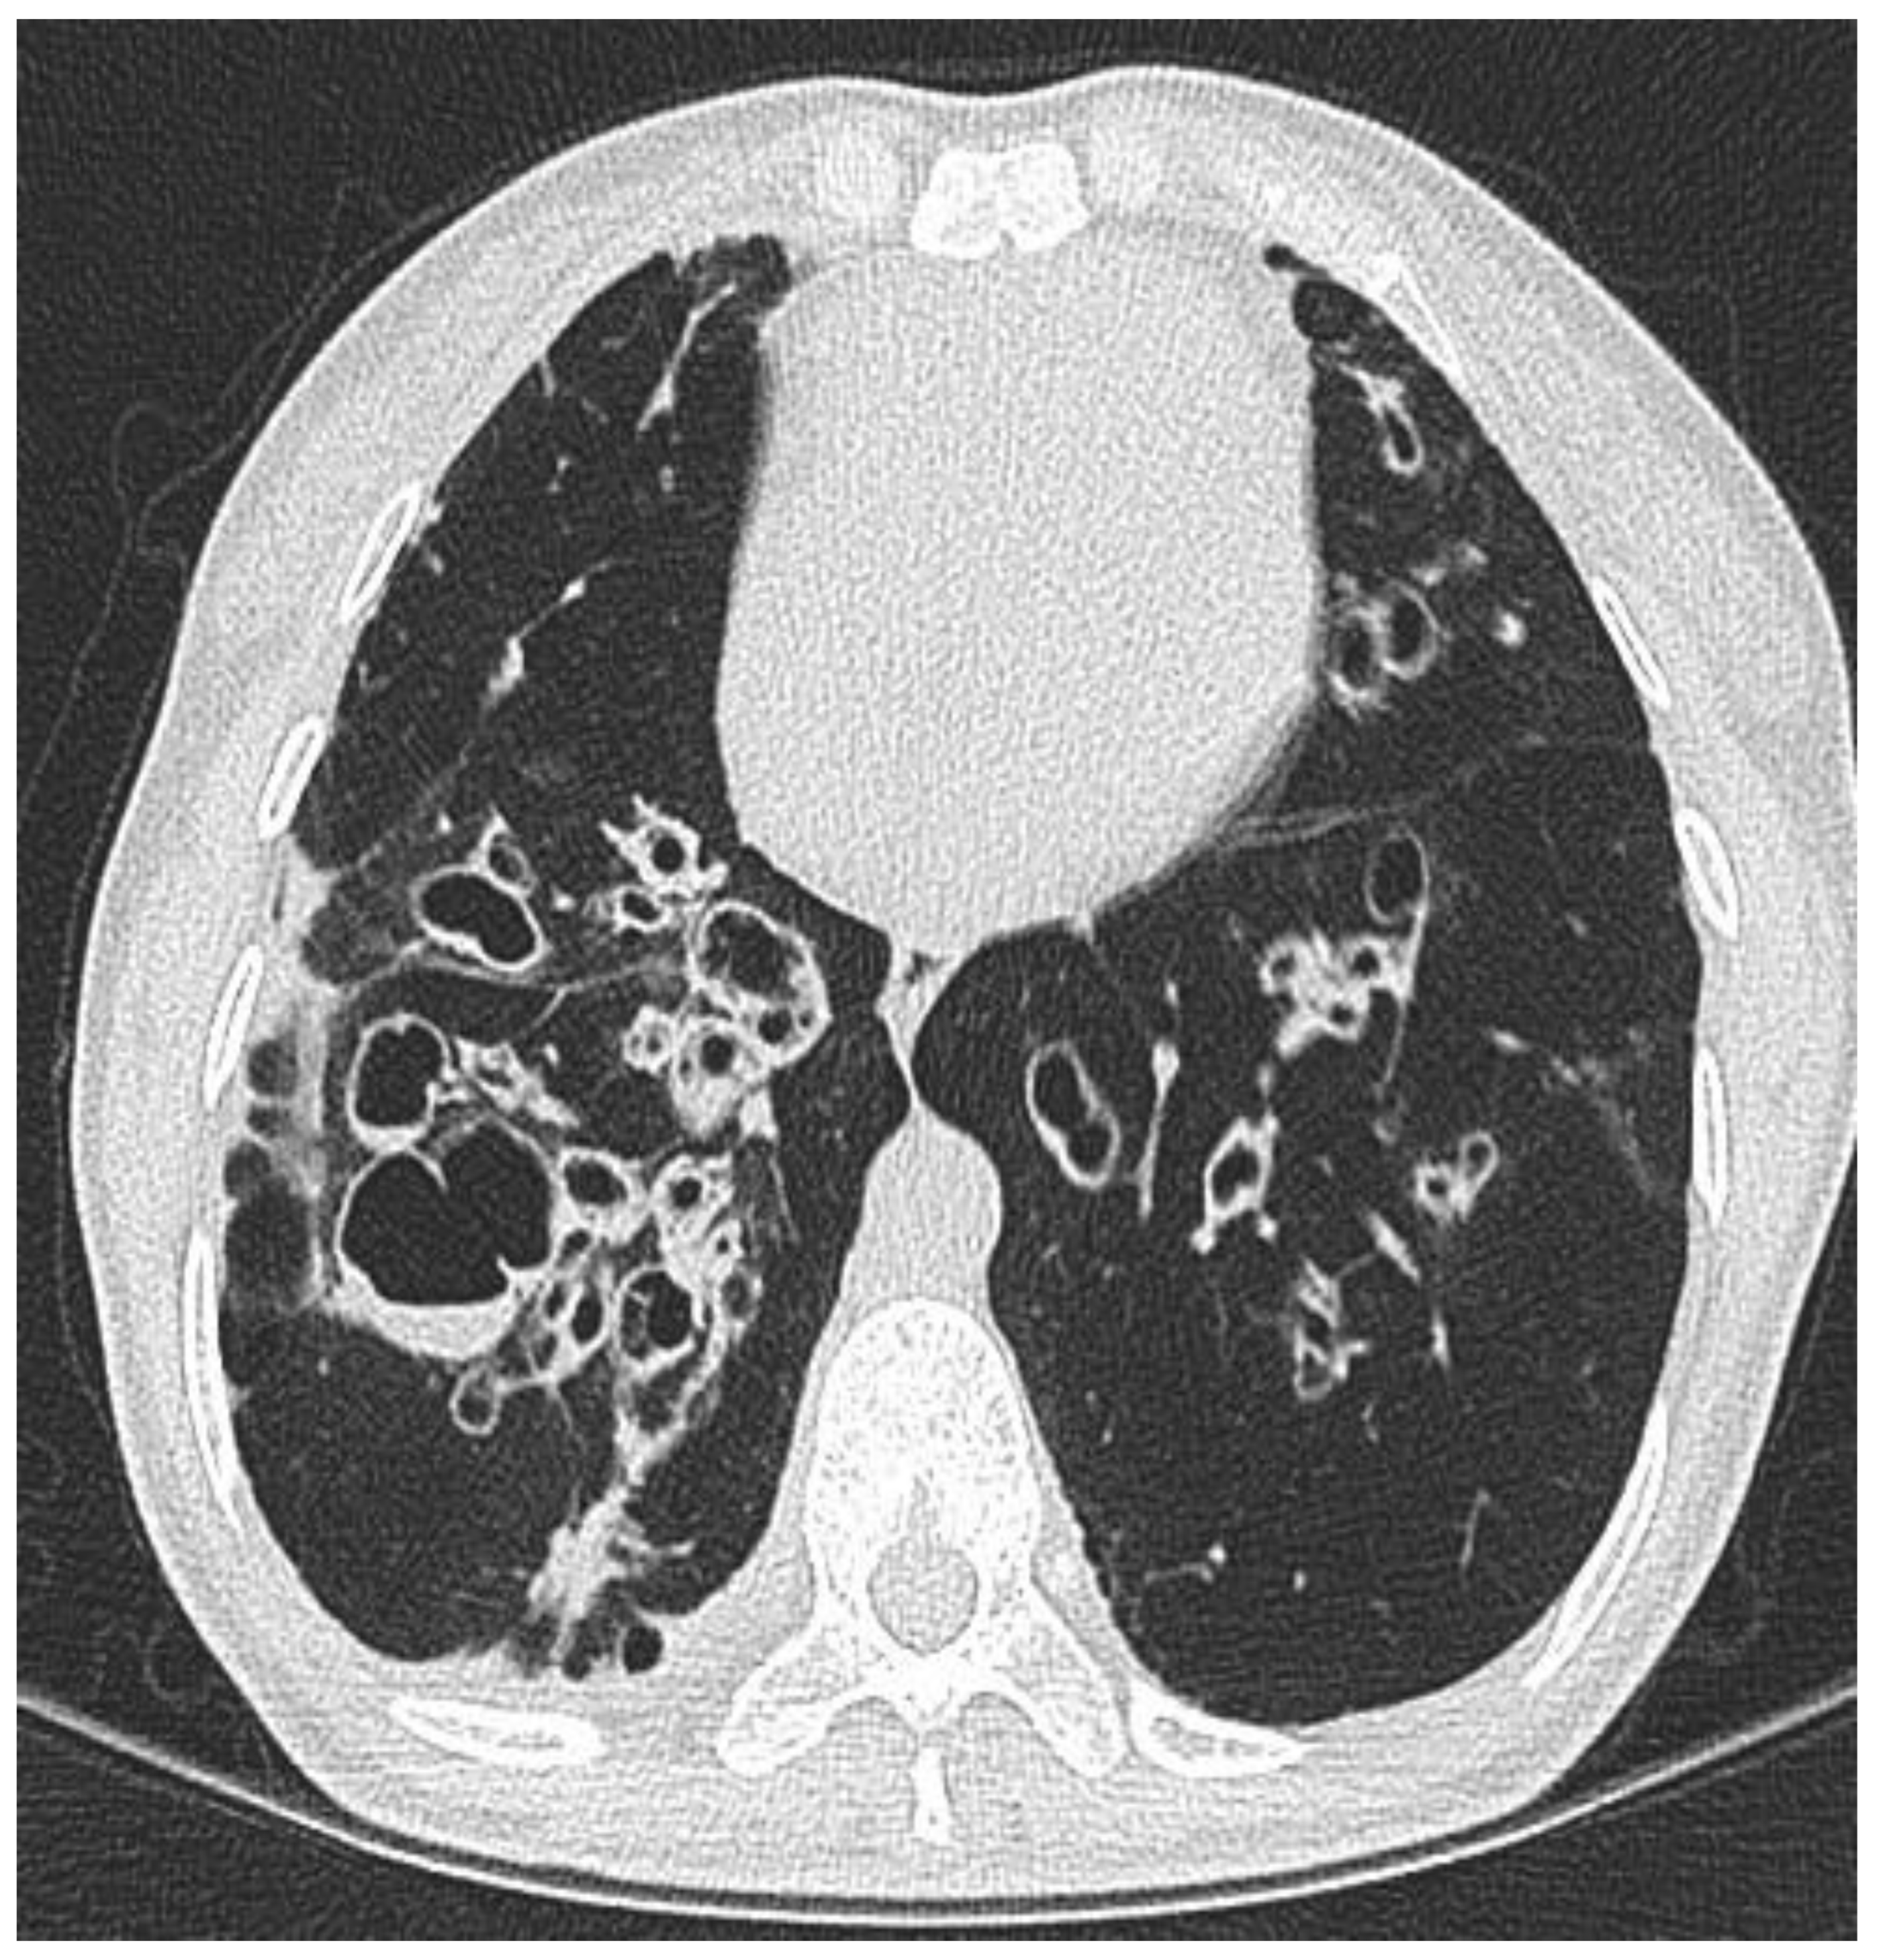

2.1. Clinical Phenotype by Radiology